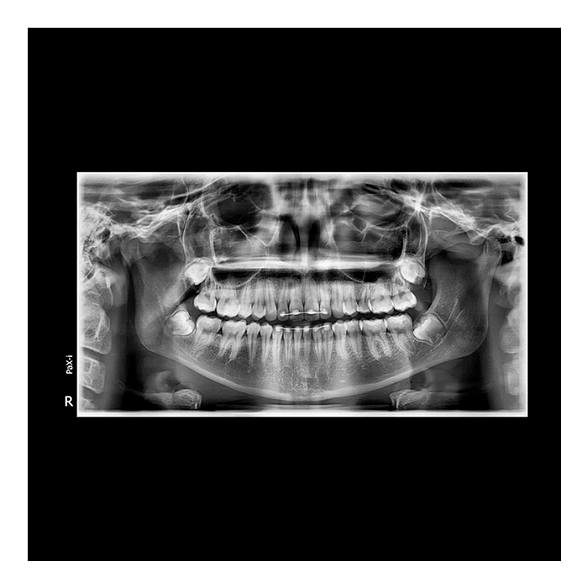

Цифровой дентальный томограф X-Radius Compact 3D — это современное решение для стоматологических клиник, стремящихся к повышению качества диагностики при разумных инвестициях. Аппарат сочетает в себе передовые технологии получения трехмерных изображений, надежность и эргономичный дизайн, что делает его идеальным выбором для широкого спектра задач: от имплантологии и эндодонтии до ортодонтии и хирургии.

Ключевой особенностью X-Radius Compact 3D является компактный размер FOV (поля обзора) 10х10 см. Этот формат оптимален для получения детализированных снимков одной или двух челюстей, области гайморовых пазух, височно-нижнечелюстных суставов. Он позволяет минимизировать дозу облучения для пациента, обеспечивая при этом всю необходимую информацию для планирования лечения.

- Высокое качество изображений: Цифровой плоскопанельный детектор обеспечивает высокое разрешение и контрастность снимков, что критически важно для оценки анатомических структур, состояния корневых каналов, положения зачатков зубов.

Чем КЛКТ отличается от обычного панорамного снимка?

Ортопантомограмма (ОПТГ) — это двухмерное суммационное изображение всей челюсти, на котором структуры могут накладываться друг на друга. КЛКТ (3D-томограф) создает трехмерную объемную модель, позволяя врачу рассмотреть область интереса под любым углом, в любой плоскости без искажений и наложений, что кардинально повышает точность диагностики.